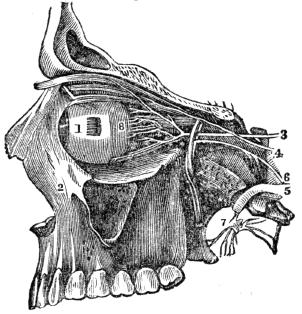

| 44. | Anatomy of the Organs of Vision, | 394 |

| 45. | Physiology of the Organs of Vision, | 404 |

| 45. | Hygiene of the Organs of Vision, | 410 |